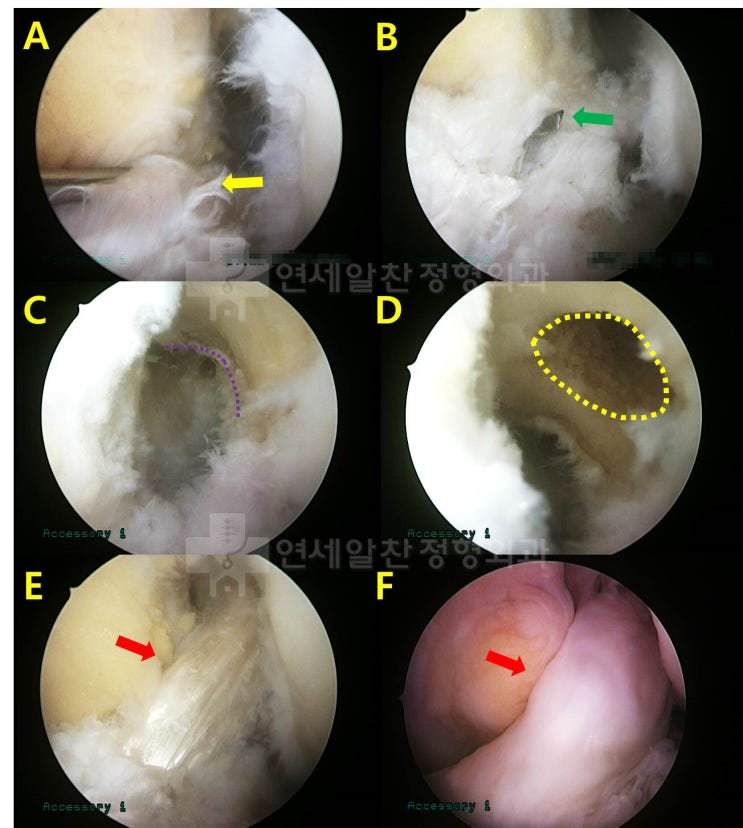

회전근개 재파열, 회전근개 재수술, 상부관절낭재건술

이번 케이스는 회전근개 일차 봉합술이 잘못되어 재파열이 일어난 경우이다. 환자는 10개월전 수술적 치료...